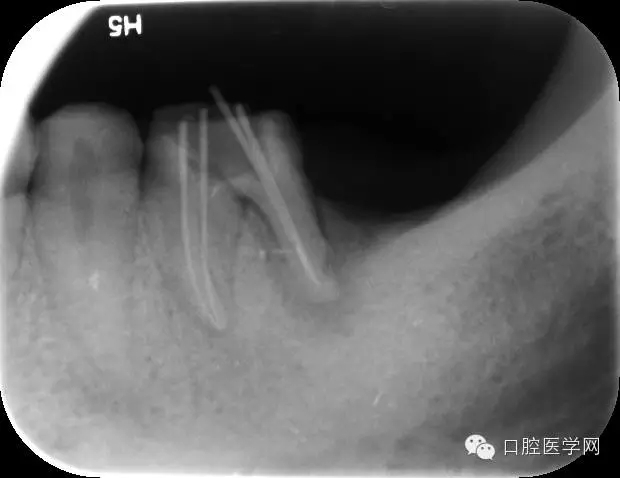

開髓引流,擴洗根管,測長;

Protaper擴根,試尖,封藥;

根充,拍片。